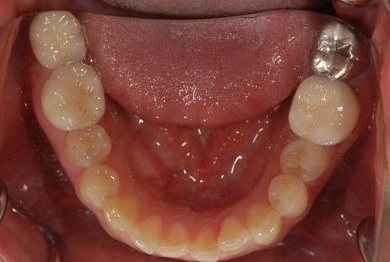

インプラント治療+セラミック治療+歯肉歯槽骨整形

| 性別/年齢 | 女性 / 38歳 | ||||||||||||||||||||||||||||||||

| 主訴 | 右下奥の欠損のため、インプラントを希望。また、左に物が挟まりやすいための治療も希望。 | ||||||||||||||||||||||||||||||||

| 治療方針 | 欠損部分を、インプラント治療にて、機能的・審美的回復を行う。 | ||||||||||||||||||||||||||||||||

| 治療内容 | インプラント1本、ジルコニアフレームオールセラミッククラウン2本(ジルコニアセラミック用土台1本)、歯肉歯槽骨整形 | ||||||||||||||||||||||||||||||||

| 総治療費 | 713,580円 | ||||||||||||||||||||||||||||||||

| 治療期間 | 10ヶ月 |